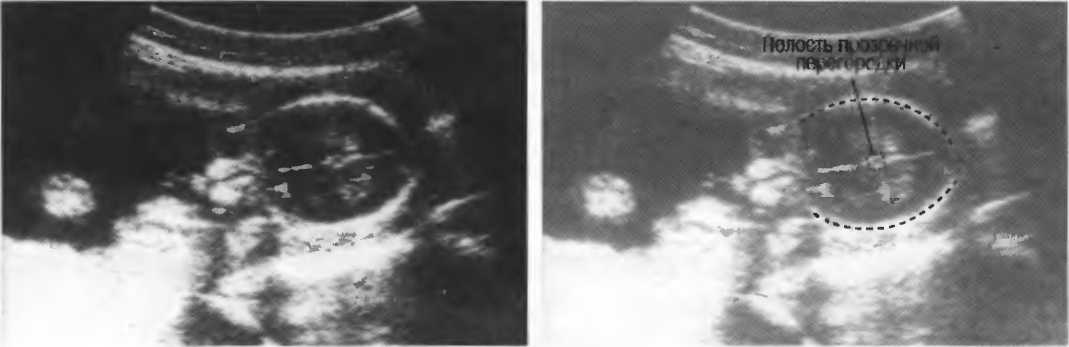

- При удовлетворительном качестве изображения можно получить изображение полости прозрачной перегородки головного мозга у 35-недельного плода (рис. 23). Этот тест можно использовать для контроля качества в случаях, когда нет фантома. Данный тест необходимо проводить каждые 3 мес.

Рис.23а. На любом приборе должна визуализироваться полость прозрачной перегородки головного мозга 35-недельного плода.

Рис.23б. На аппарате высокого класса полость может визуализироваться в более ранние сроки беременности.